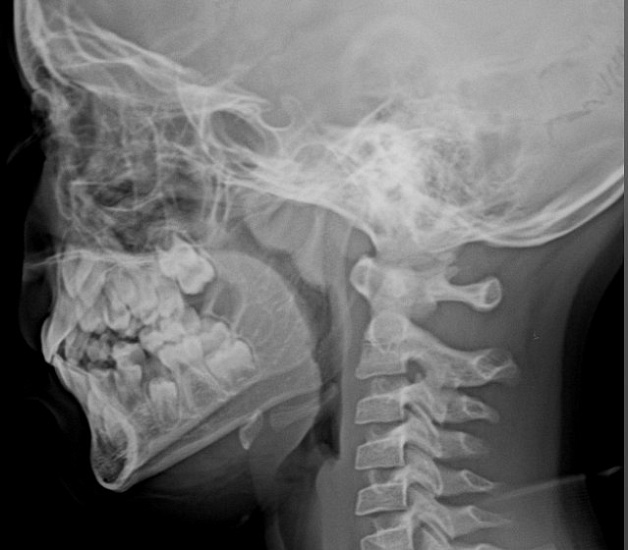

Рентгенография носоглотки

Рентгенография носоглотки – важный метод прицельного исследования, который позволяет оценить состояние носоглотки и ее просвет.

Диагностическая услуга выполняется в одной проекции.

Показания для проведения рентген носоглотки:

• нарушение носового дыхания;

• воспалительные процессы, деформации и травмы носоглотки;

• подозрение на наличие аденоидных вегетаций.